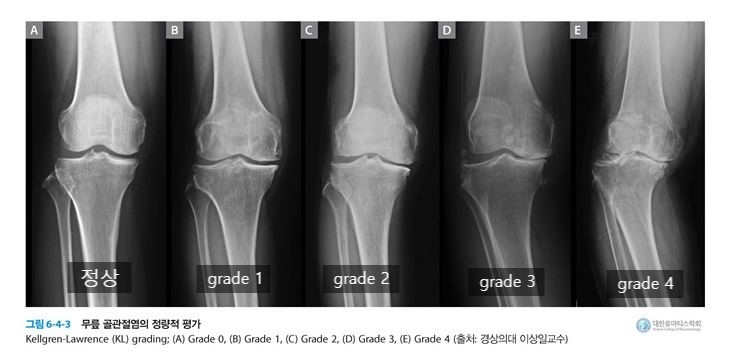

- K-L Grade(Kellgren Lawrence 분류법) : X-ray 사진 상에서 관절 간격의 감소를 통해 관절의 골극형성이나 연골 소실 등의 이상소견을 나타내는 평가지표로 Grade 0 ~ 4까지 5단계로 분류한다.